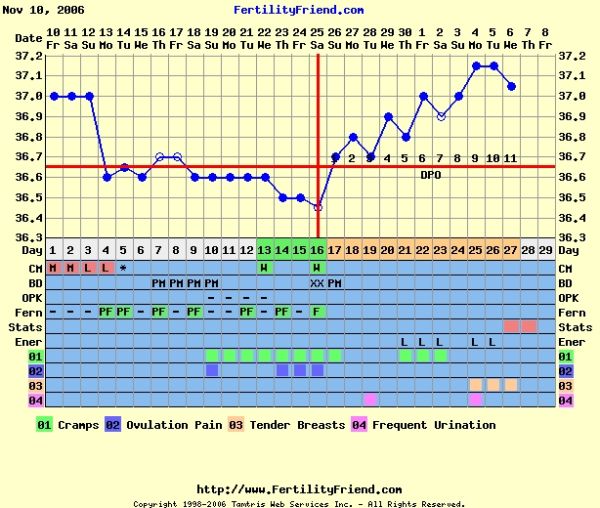

Bocsi, nem tudom már ki írt az összevissza ciklusról. Nekem nagyon szépen beállt 26-27 napra, erre az előzőt sikerült kihúznom 36 napig. Képzelhetitek. Örüljetek hogy nem voltam itt